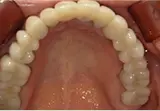

CASE

| 年齢/性別 | 40代女性 |

| 主訴 | 右上の詰め物が取れた |

| 治療内容 | 歯周病とむし歯の治療を目的に来院。左下の奥歯は根の状態が悪く、病変も大きかったため保存が困難と判断。 インプラント治療を実施しました。 |

| 治療期間 | 4か月 |

| 費用 | 566,500円税込 |

| リスク・副作用 | 炎症反応によって術後に腫れが生じることがあります。その程度は、手術の範囲や方法によって異なりますが、多くの場合、時間の経過とともに徐々に治まります。 ごく稀に、下顎奥歯の外科手術後に、唇や顎に痺れを感じることがあります。 |